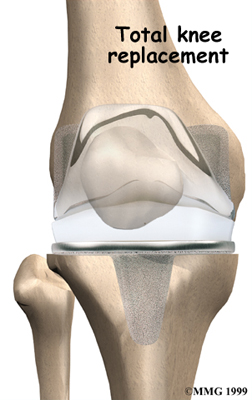

Artificial Knee Replacement

An artificial knee replacement is the ultimate solution for advanced knee OA.

Surgeons prefer not to put a new knee joint in patients younger than 60. This is because younger patients are generally more active and might put too much stress on the joint, causing it to loosen or even crack. A revision surgery to replace a damaged prosthesis is harder to do, has more possible complications, and is usually less successful than a first-time joint replacement surgery.

Related Document: FYZICAL Sarasota Downtown's Guide to Artificial Joint Replacement of the Knee